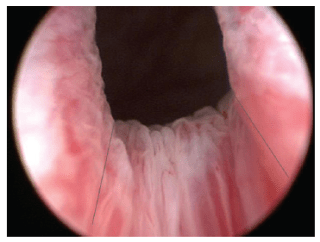

Como una primera aproximación terapéutica y en virtud a las posibles causas neurológicas de esta patología, sería imperativo iniciar una terapia con bloqueantes alfa adrenérgicos. Cabe mencionar que muchos de los paciente no mejoran con esta medida, siendo tributarios entonces a la cirugía endoscópica mediante la incisión transuretral del cuello vesical. La resección transuretral del cuello no debería plantearse como una medida estándar, pues esta descrito un gran número de pacientes con esclerosis de cuello post operatoria.

| Detalle de incisión |